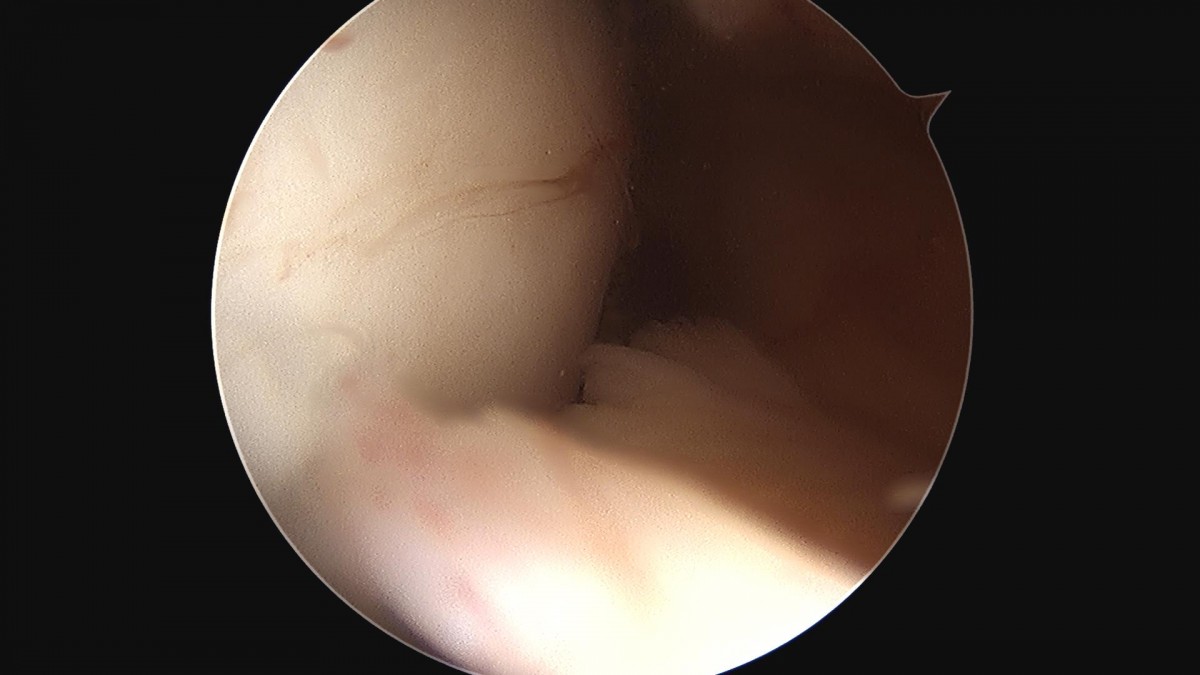

이재상 원장님 무릎 반월상 연골판 절제술 박진O 환자

8b0c7da4bf0a0c139df98fc62b3e688e_1702369986_0427.jpg